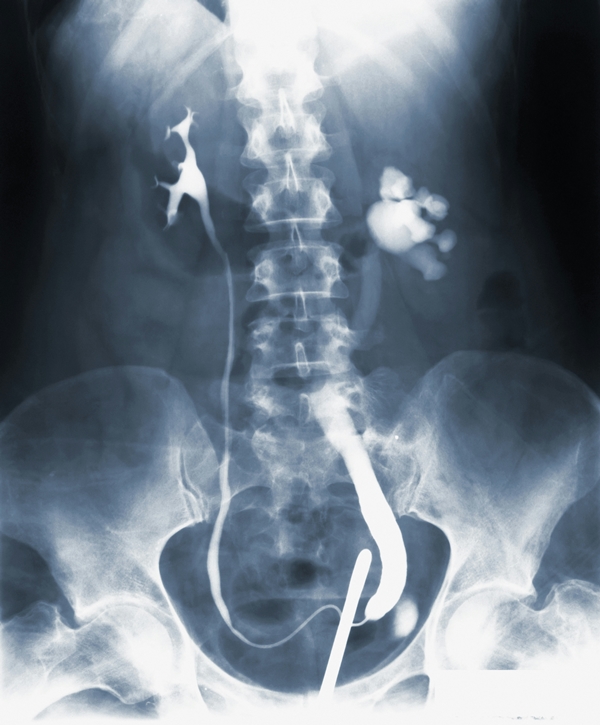

탈장이란(장기가 제자리를 벗어남) 말 그대로 장이 있어야 할 벽(복벽)에 구멍이 나거나 약해지면서 그 틈으로 장기가 밀려 나오는 현상이에요. 우리 몸의 복벽은 아주 튼튼한 타이어 같은 구조인데, 노화나 무리한 운동으로 타이어에 구멍이 뚫리면 안쪽의 장기가 삐져나오는 거죠.

최근에는 복강경(배에 작은 구멍을 내는 수술)으로 흉터 거의 없이 금방 고칠 수 있으니 너무 겁먹지 마세요. 병원에 가면 의사 선생님이 튀어나온 부위를 만져보거나 기침을 시켜보실 거예요. "에취!" 할 때 장기가 툭 튀어나오는 게 느껴지면 진단 끝! 확실한 확인을 위해 초음파 검사를 하기도 하니, 이상하다 싶으면 바로 외과 간판을 찾으시는 게 지갑과 건강을 지키는 길입니다.

가장 흔한 건 사타구니 쪽에 생기는 서혜부 탈장 증상(사타구니 부위 탈장)이에요. 전체 탈장의 70% 이상을 차지할 만큼 지분율이 높죠. 남성분들은 고환 쪽까지 묵직한 통증이 내려오는 탈장 증세 고환 통증을 겪기도 해요. 이건 장기가 내려오면서 고환으로 가는 통로를 건드리기 때문인데, 민망해하지 말고 빨리 병원을 찾아야 해요.